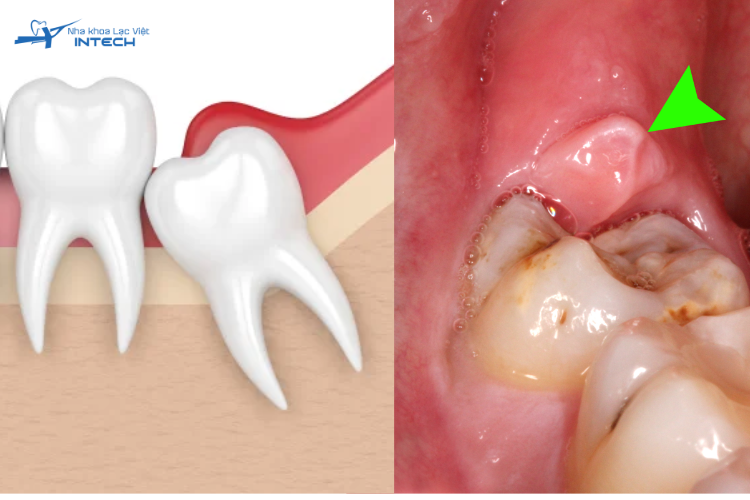

Viêm lợi trùm răng khôn là một phản ứng viêm nhiễm thường gặp, phát sinh khi răng khôn (răng số 8) cố gắng mọc trong điều kiện không gian hạn chế ở cuối cung hàm. Do vị trí đặc biệt này, răng khôn thường không có đủ chỗ để mọc thẳng đứng như các răng khác, dẫn đến xu hướng mọc lệch, nghiêng, hoặc chỉ nhú lên được một phần. Tình trạng mọc răng không hoàn chỉnh này tạo ra một cấu trúc gọi là "túi lợi trùm".

Răng khôn mọc lệch khiến lợi sưng lên và viêm

Túi lợi trùm là một vạt nướu mềm bao phủ lên một phần bề mặt răng khôn. Khoảng trống giữa vạt lợi và răng là nơi lý tưởng để các mảnh vụn thức ăn và vi khuẩn tích tụ. Vệ sinh khu vực này thường khó khăn do vị trí khuất sâu và sự che chắn của lợi.

Sự tích tụ liên tục của vi khuẩn trong môi trường yếm khí này kích thích phản ứng viêm, gây ra các triệu chứng sưng, đau và có thể có mủ, đặc trưng cho viêm lợi trùm răng khôn.